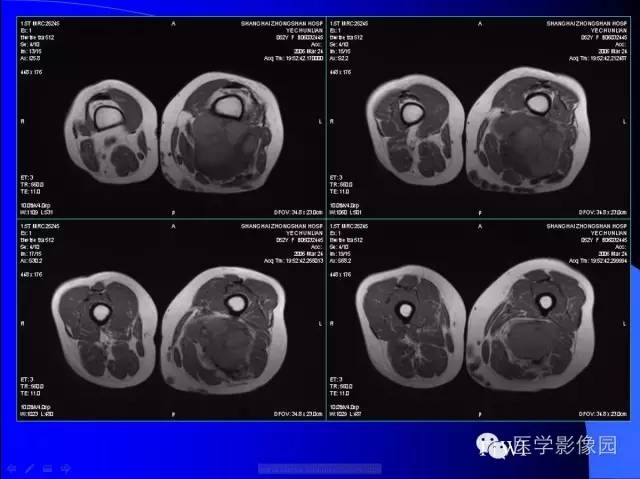

【病例】大腿恶性孤立性纤维瘤1例MR

病史:女,52岁,左大腿包块30年,逐渐长大。

孤立性纤维瘤起源于弥漫分布于人体结缔组织中CD34阳性的树突状间叶细胞。多见于头颈部、上呼吸道、腹腔和周围软组织。发病高峰40~ 60 岁, 女性多见。临床上多数病例表现为局部缓慢生长的无痛性包块。随着包块的增大, 会出现相应部位的压迫症状。孤立性纤维瘤多数病例临床上呈良性经过, 约10% 的非典型性和恶性孤立性纤维瘤局部复发率或远处转移率较高(80% )。